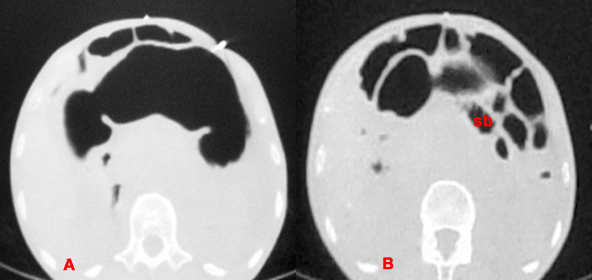

Air initially distends the stomach (A) but eventually will leak into the small bowel (sb) and peritoneal cavity (B), so continued insufflation is necessary.